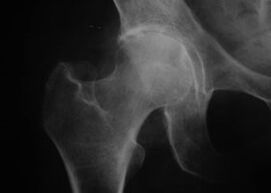

Appearance of a joint with osteoarthritis

Coxathrosis, arthrosis of the hip joint

With this disease, a classic clinical picture of osteoarthritis is observed.

The first symptom of coxarthrosis is discomfort in the hip joint after physical activity.

As coxarthrosis progresses, pain increases, stiffness and limited mobility occur.

Patients with a severe form of coxarthrosis protect the affected limb, avoid stepping on it and, when standing still, choose positions in which the pain is least noticeable.